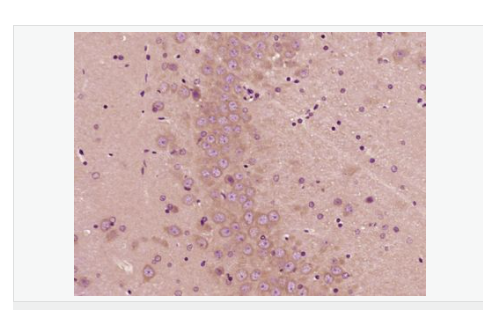

| 產(chǎn)品應(yīng)用 | ELISA=1:5000-10000 IHC-P=1:100-500 IHC-F=1:100-500 IF=1:100-500 (石蠟切片需做抗原修復(fù)) not yet tested in other applications. optimal dilutions/concentrations should be determined by the end user. |

| 產(chǎn)品介紹 | PBR (Peripheral type Benzodiazepine Receptor) is a ubiquitous protein (18 kDa) found in most steroidogenic tissues. It is located primarily in the outer mitochondrial membrane of steroid producing tissues and is found in association with a 34 kDa voltage dependent anion channel protein (VDAC). PBR interacts with some benzodiazepines and has different affinities than its endogenous counterpart. PBR appears to be a key factor in the transport of cholesterol from the outer to the inner mitochondrial membrane to permit the initiation of steroid hormone synthesis. It is thought to be part of the mitochondrial permeability transition pore (PT) and to be involved in apoptosis. It is speculated that patients with congenital lipoid adrenal hyperplasia, who cannot make any steroids, might have a genetic lesion in BZRP. A short form, PBRS is also expressed in the same tissues, but at a level about ten times that of PBR. Function: Responsible for the manifestation of peripheral-type benzodiazepine recognition sites and is most likely to comprise binding domains for benzodiazepines and isoquinoline carboxamides. May play a role in the transport of porphyrins and heme. Plays a role in the transport of cholesterol across mitochondrial membranes in steroidogenic cells. Subcellular Location: Mitochondrion membrane. Tissue Specificity: Found in many tissue types. Expressed at the highest levels under normal conditions in tissues that synthesize steroids. Similarity: Belongs to the TspO/BZRP family. SWISS: B1AH88 Gene ID: 706 Database links: Entrez Gene: 706 Human Entrez Gene: 12257 Mouse Omim: 109610 Human SwissProt: B1AH88 Human SwissProt: P30536 Human SwissProt: P50637 Mouse Unigene: 202 Human Unigene: 1508 Mouse Important Note: This product as supplied is intended for research use only, not for use in human, therapeutic or diagnostic applications. 地西泮結(jié)合抑制因子; DBI能拮抗安定物質(zhì):diazepam與腦突觸膜相結(jié)合 ,故稱之為安定結(jié)合抑制蛋白(DBI),地西泮結(jié)合抑制因子(diazepam binding inhibitor,DBI)具有抑制由葡萄糖誘導(dǎo)的胰島素分泌、促進膽固醇跨線粒體膜轉(zhuǎn)運和調(diào)節(jié)脂肪酸合成與代謝等多種生理功能。 |